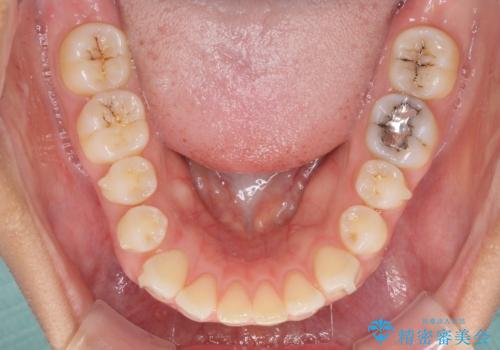

受け口傾向の前歯 すきっ歯の改善

舌癖を改善したことで、隙間や突出感を改善することができました。

隙間は後戻りしやすいため、舌側を細いワイヤーで固定することとしました。